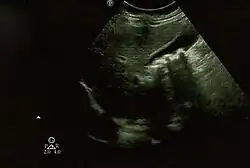

| Biliary pseudolithiasis as seen on ultrasonography. The gallbladder contains gallstone mimics resulting from ceftriaxone therapy. |

Biliary pseudolithiasis is an unusual complication of ceftriaxone where the drug complexes with calcium and mimics gallstones.[1][2] It is reversed when ceftriaxone administration is stopped.[2] It was first described in 1988 by Schaad et al. as "reversible ceftriaxone-associated biliary pseudolithiasis".[2][3] Ceftriaxone has been frequently associated with biliary sludge or biliary pseudolithiasis in subsequent reports.[3] Ceftriaxone is excreted primarily through the urine, but also through the bile, up to 40% of its excretion, with concentrations in the bile 20-150 times higher than in the serum.[3][4] It forms a calcium salt in the gallbladder, which can exceed its solubility and create precipitates that resemble gallstones on ultrasonography.[3] The incidence of pseudolithiasis in children treated with ceftriaxone is up to 25%, but most patients are asymptomatic.[3][4] Risk factors for biliary pseudolithiasis include age greater than 24 months, gram-negative sepsis, high doses of ceftriaxone, hypercalcemia, surgery, and decreased bile flow/increased ceftriaxone excretion in bile.[3][4][5] Conservative management with serial ultrasounds is recommended until the "stones" completely resolve.[3] If associated with ceftriaxone, it resolves on average about 2 weeks after the ceftriaxone is stopped.[4]